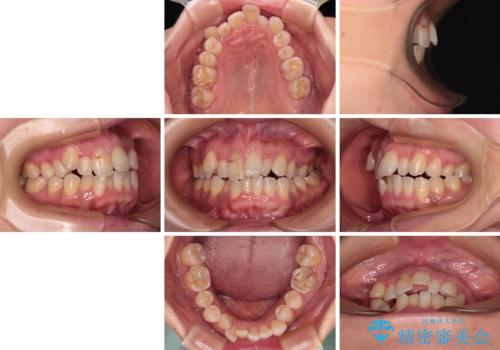

- 前歯のデコボコと咬み合わせの悪さを気にして来院された患者様です。

下顎骨が左側にズレて成長してしまったため、左側の咬み合わせが上下反対になっている状態でした。

骨格的なズレは歯列矯正のみでは改善できず、骨切除が必要となります。

そこまでの処置は望んでいらっしゃらなかったため、歯列矯正でのカムフラージュにより咬み合わせを改善することとしました。

予想通り左側の咬み合わせの調整に苦労をしましたが、最終的には違和感のない咬み合わせを達成することができました。